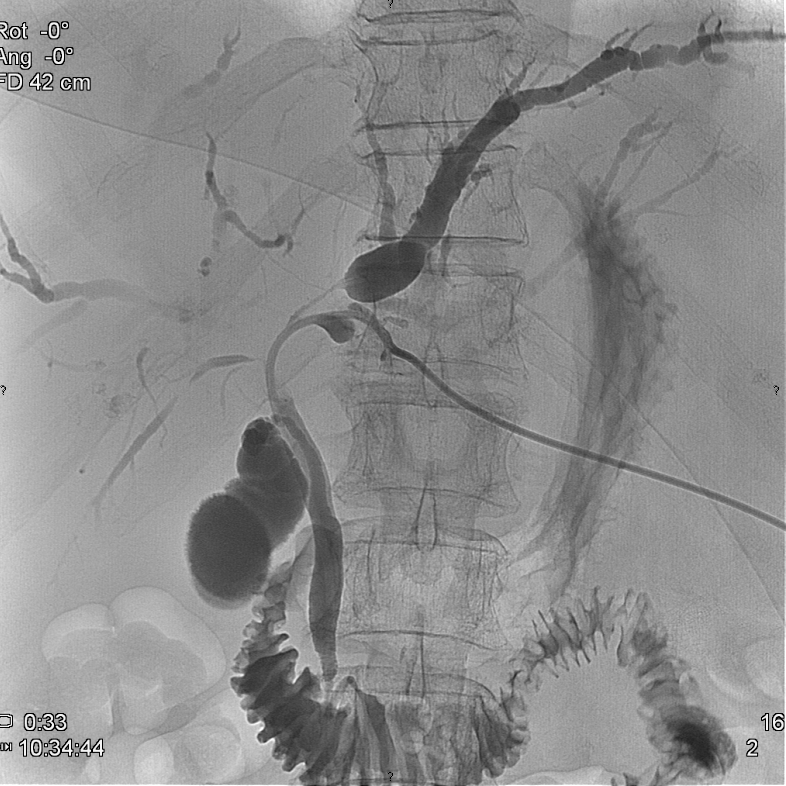

After a diagnostic PTC is successfully performed and a guide wire is positioned over the stenotic or occluded segment of the choledochal duct an external-internal drain (PTD) can be installed. (Figure 23.) If desired, a self expanding metallic stent could be used to override the stricture (Figure 24.)

Image

Figure 23. – PTD (Percutaneous transhepatic external-internal drainage)

Figure 24. – Choledochal stent, palliative procedure do pancreatic head tumor

If one cannot pass the biliary stenosis in the initial attempts, the placement of a temporary external drainage is advisory to control the biliary congestion and cholangitis. Later during a second session the insertion of an external-internal drain will be possible.

In special cases separate catheter insertion and stenting of both the left and right hepatic ducts might be necessary. This depends on the extent of the pathologic lesion (tumor or inflammation).

In case of a malignant stenosis the use of covered stents can prolong the passage in the tumor bound segment of the choledochal duct.